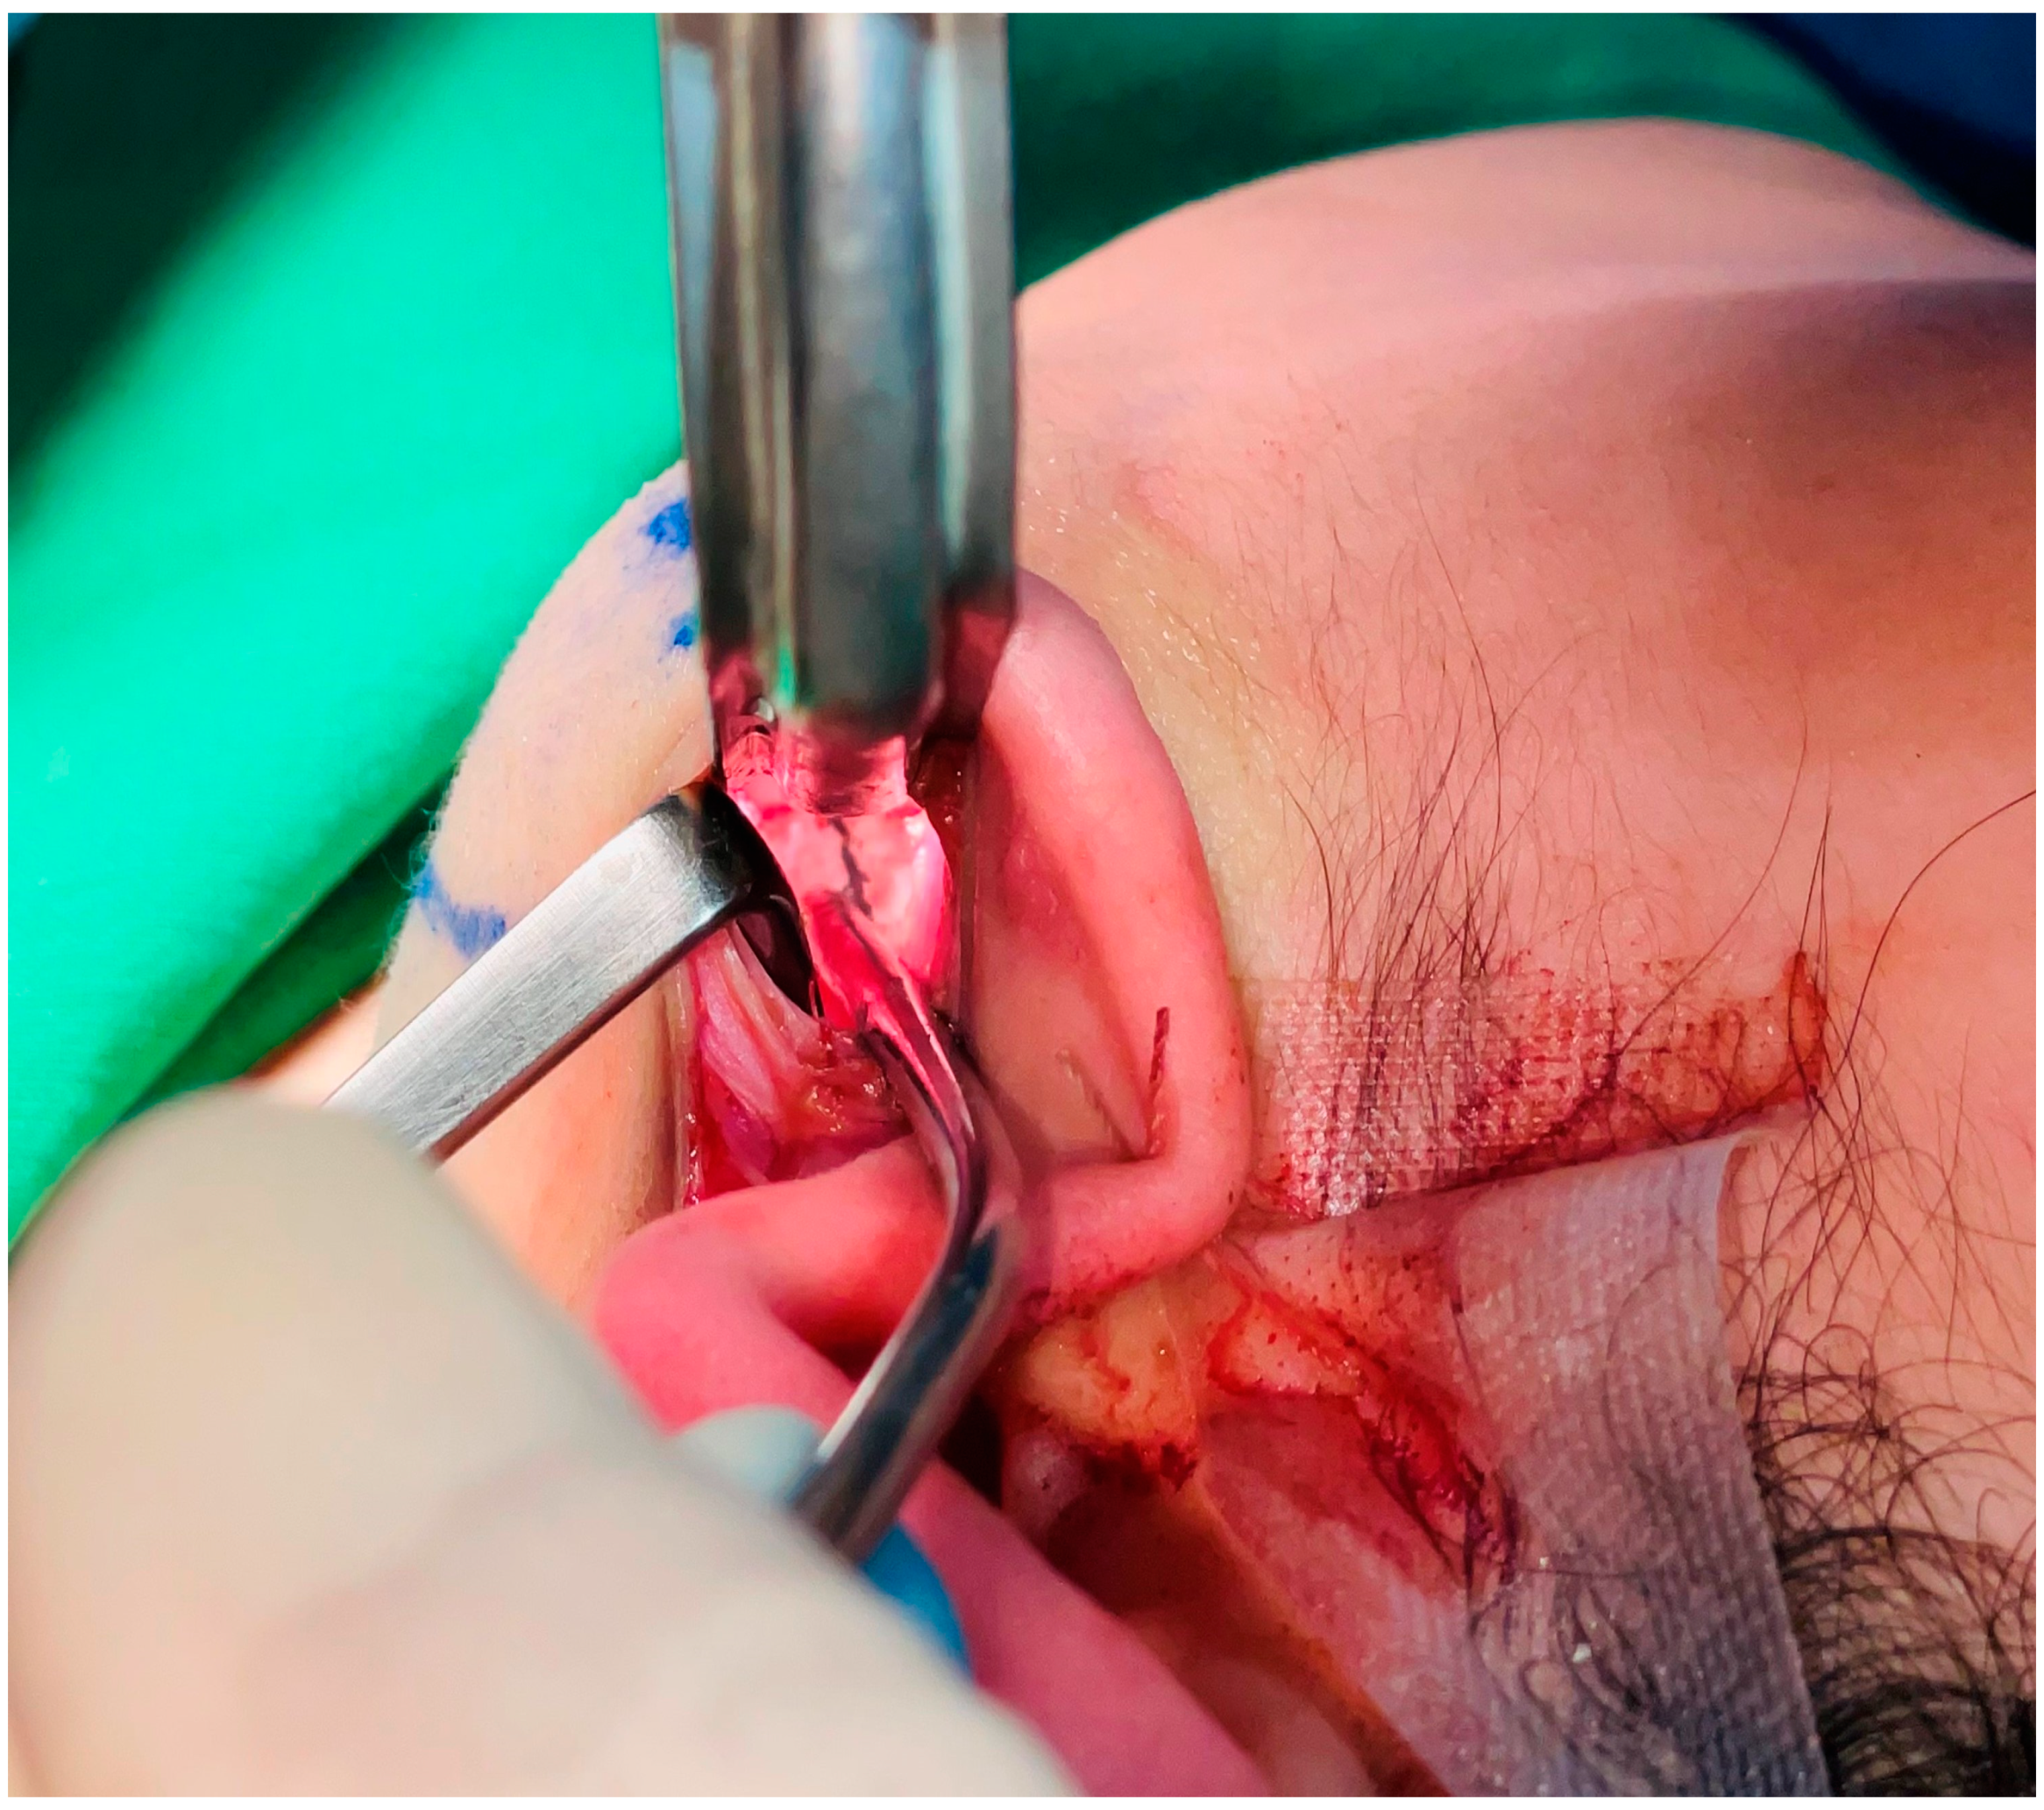

2.1. Surgical Techniques